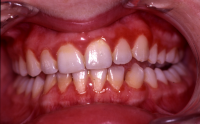

En volymökning av mjukvävnaden kring tänderna som är associerad med intag av läkemedel tillhörande grupperna antiepileptika, immunosuppressiva läkemedel och kalciumblockerare.

Inflammation är den utlösande faktorn som driver tillväxten av mjukvävnaden därför är plackkontroll av största vikt.

Förekomst av gingivala hyperplasier med djupa tandköttsfickor och svåra hygienförhållanden som följd.

Läkemedelsinducerad gingival hyperplasi: